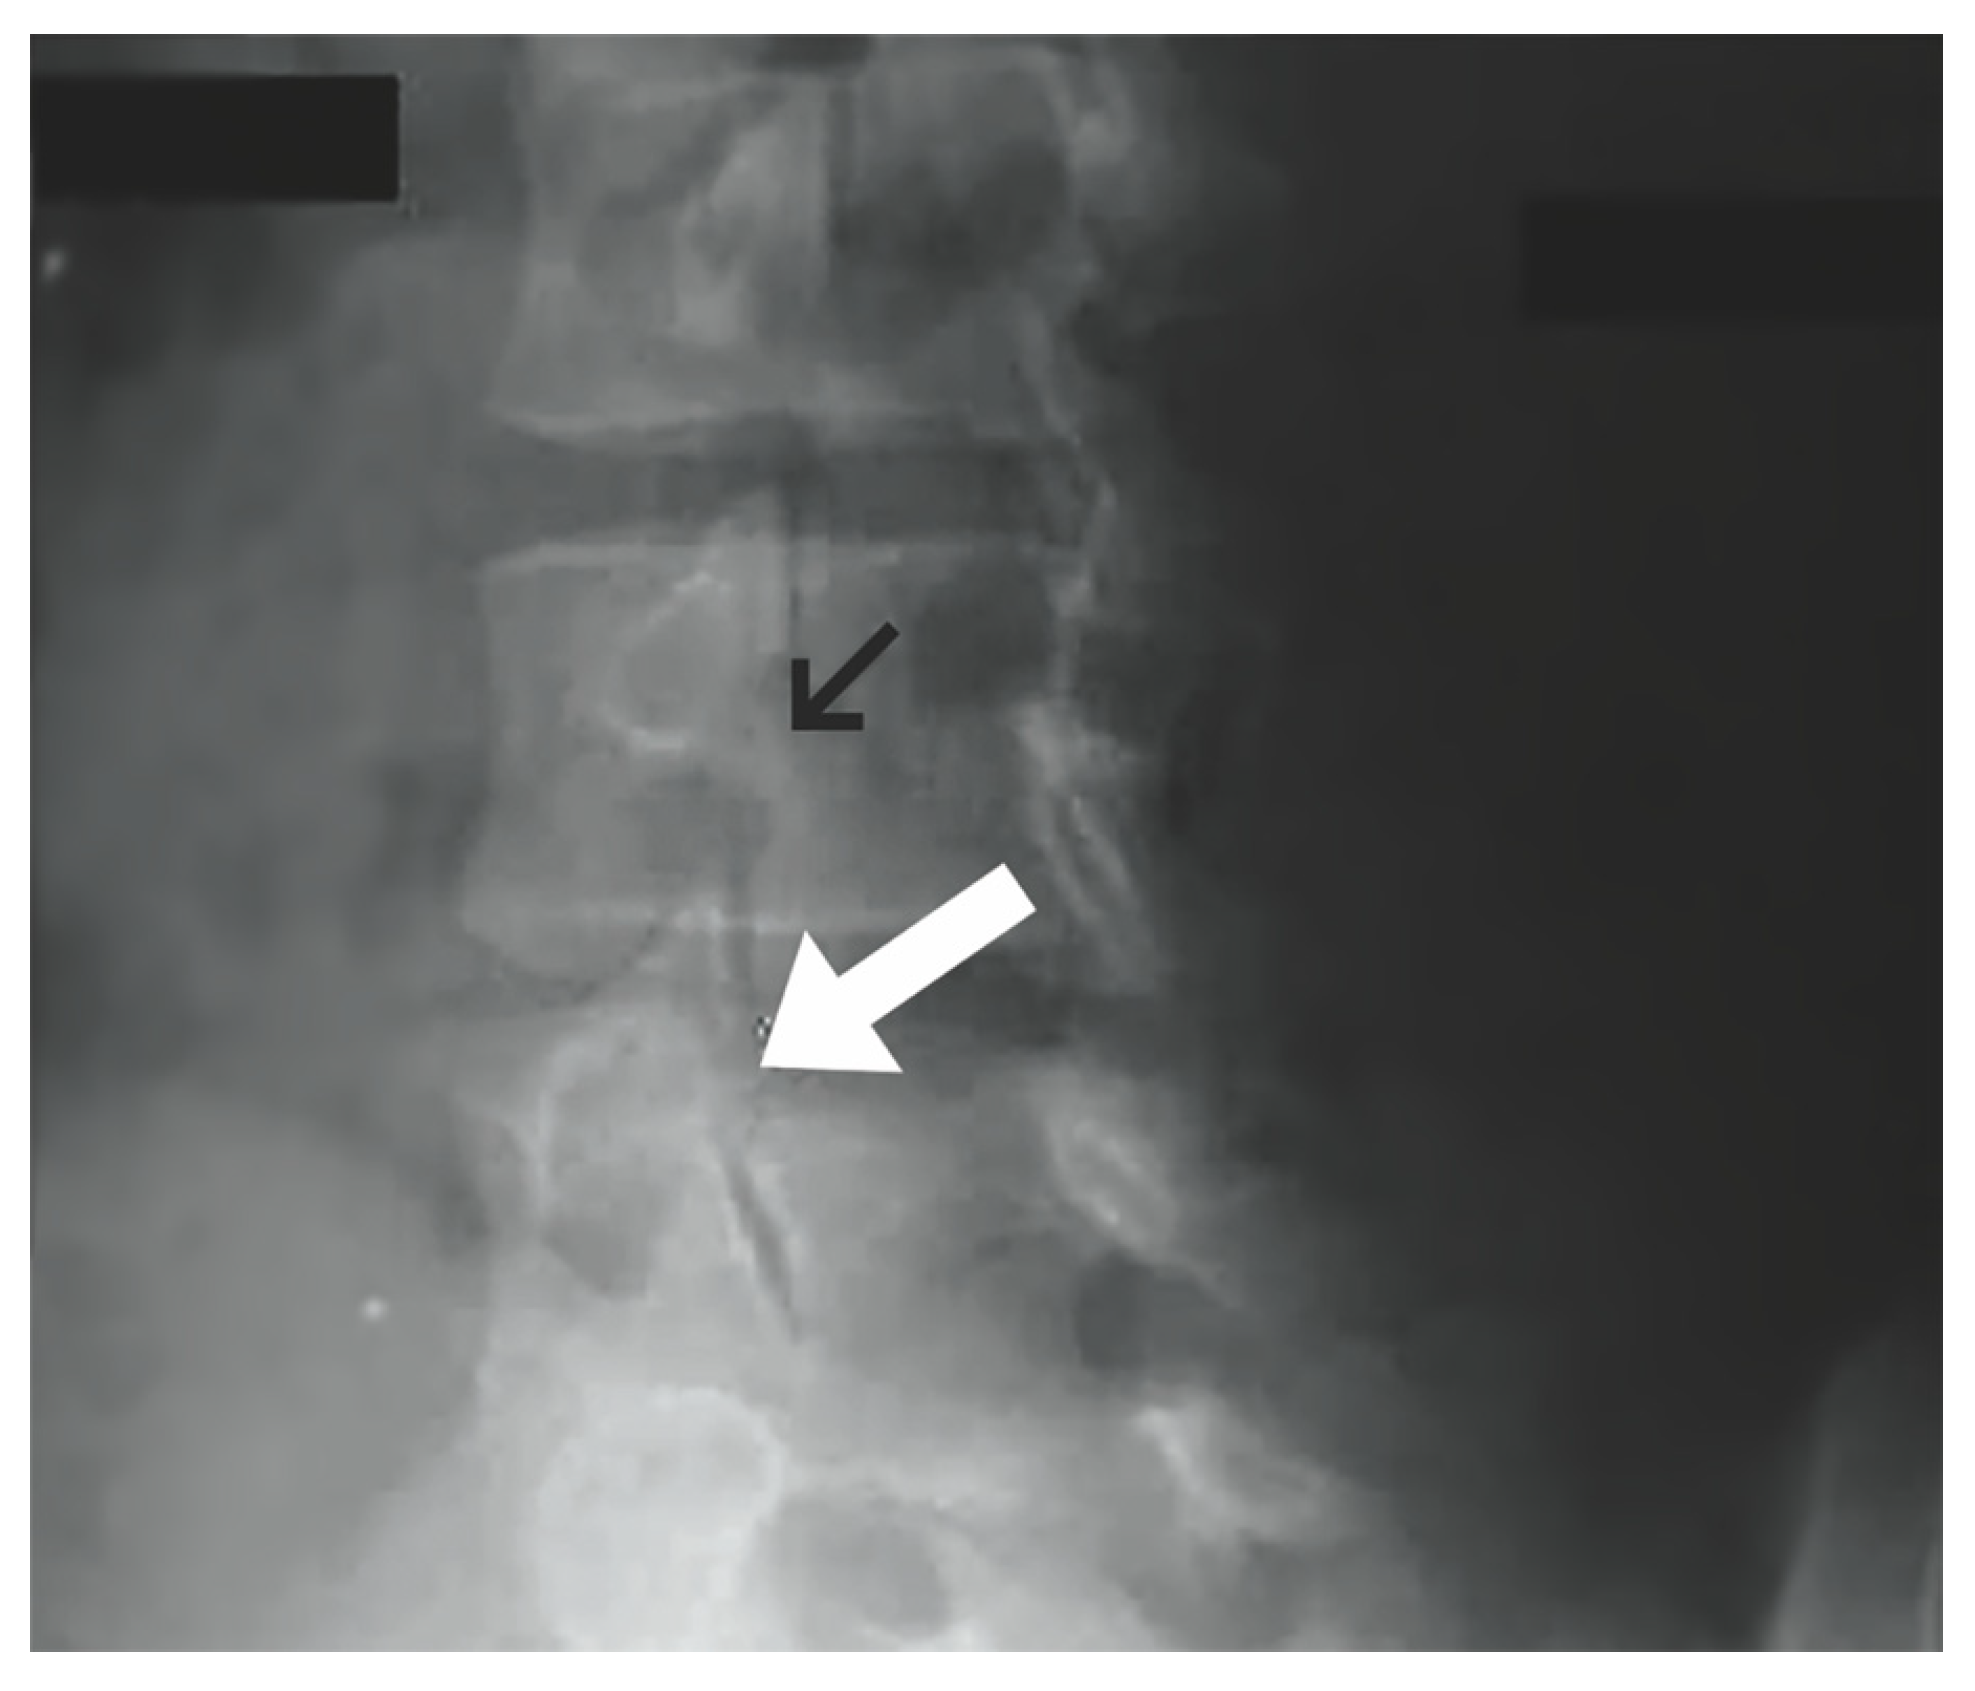

1.5. Imaging

- Leone, A.; Cianfoni, A.; Cerase, A.; Magarelli, N.; Bonomo, L. Lumbar spondylolysis: A review. Skelet. Radiol. 2011, 40, 683–700. [Google Scholar] [CrossRef] [PubMed]

- [Figure, Oblique Plain Radiograph of the…]—StatPearls—NCBI Bookshelf. Available online: https://www.ncbi.nlm.nih.gov/books/NBK538292/figure/article-26700.image.f1/?report=objectonly (accessed on 28 October 2023).